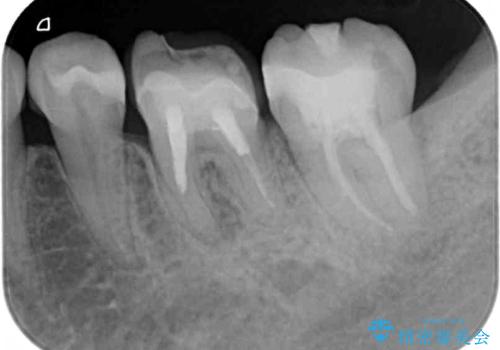

詰め物と歯に隙間ができており、既に根管治療をされた歯であったため、フルジルコニアクラウンにて補綴治療をすることとしました。

咬んだときに違和感があるとのことだったので、根管治療を事前におこなうこととしました。